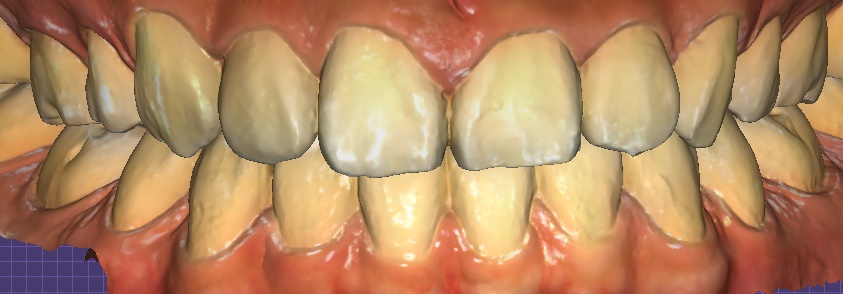

① Digital scan & design

– Precise data acquisition with an intraoral scanner → 3D design and simulation

Object Zero laminate simulation

② Minimal reduction and impression taking

– After barely touching the teeth and shaping them as little as possible, a precise impression was taken